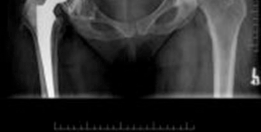

Discover the latest medical recommendations for Solving Severe Acetabular Bone Loss with Cup-Cage Reconstruction. Acetabular bone loss, often due to aseptic loosening of hip implants, manifests as acute groin pain and inability to weight bear. Radiological assessment typically reveals severe osteolysis of the ilium and ischium. Diagnosis centers on the extent of acetabular bone loss. Treatment, such as cup-cage reconstruction, aims to address significant defects and restore stability in complex revision total hip arthroplasty cases.

The classification of acetabular bone loss is critical for surgical planning. The Paprosky classification is widely adopted, categorizing defects based on the integrity of the host bone and the direction of component migration.

The American Academy of Orthopaedic Surgeons classification also delineates defects based on morphology, including cavitary, segmental, combined, protrusio, and pelvic discontinuity. Severe bone loss, particularly Paprosky Type 3A and 3B defects, frequently necessitates reconstruction techniques that go beyond conventional cementless hemispheric components with augments. Historically, structural allografts and isolated anti-protrusio cages were utilized; however, these demonstrated high long-term failure rates due to graft resorption and mechanical fatigue failure of the cages in the absence of biologic fixation.

The cup-cage construct, utilizing a cemented polyethylene liner within a metal cage that bridges a highly porous primary acetabular shell, has emerged as a robust solution for these challenging cases. This reconstructive strategy aims to achieve immediate mechanical stability, bridge critical bone defects, and provide a stable environment for potential host bone ingrowth into the porous shell, thereby restoring hip biomechanics and function. The increasing prevalence of revision total hip arthroplasty in an aging population underscores the importance of mastering these complex reconstructive techniques.

Meticulous preoperative planning is the cornerstone of successful cup-cage reconstruction. Standard radiography must include an anteroposterior pelvis view, an anteroposterior view of the affected hip, and Judet oblique views (iliac and obturator) to assess the integrity of the anterior and posterior columns. The presence of a pelvic discontinuity is often suggested by a visible fracture line through the acetabulum, medial translation of the inferior hemipelvis, or a break in the Kohler line.